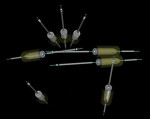

The finalized virtual implant plan (Figure 8 through Figure 12) consisted of two 10-mm implants and one 13-mm implant in the maxillary anterior region, which engaged the cortical bone at the inferior border of the nasal cavity. The plan called for two 18-mm implants to be placed in the pterygomaxillary31,32 region at an approximately 45-degree angle to the occlusal plane. These pterygomaxillary implants would provide posterior support for the restoration and eliminate a posterior cantilever.33-36 In order to shorten the span between the three anterior and two posterior implants, three zygoma implants were planned on the pre-surgica lcomputer model to transect through the sinus cavity and engage the zygoma bone. All implants in the virtual planning were external-connection regular-platform implants (Brånemark® System, Nobel Biocare).

Once the zygoma implants were positioned virtually, the sizes of each zygoma implant were recorded and screenshots of the planning were taken. The virtual zygoma implants were then switched to standard-length implants in the exact same axis (Figure 13). The appropriate surgical template sleeve accompanied the standard-length implants, which could be incorporated into the surgical template. While these standard Brånemark sleeves would not permit actual zygomatic implant placement, they would enable the surgeon to create a starting point for the access of the zygoma position into the alveolar bone. This provided the ability to put the coronal aspect of the zygoma implant in the best prosthetic position, which is a tremendous advantage for laboratory construction of the final prosthesis. It also gives the surgeon an opportunity to study the 3-D anatomy of the patient prior to the surgery.

The standard-length implants were installed following the normal guided-surgery protocol.23-30 The pterygomaxillary implant on the patient’s left side had much higher primary stability than anticipated from the virtual planning; therefore, only one of the two zygoma implants was installed on that side. Then, using a 3-mm twist drill through the surgical template (Figure 14), the zygomatic implant entry through the alveolus into the sinus was made. The surgical template was then removed. A crestal-palatal incision was then made connecting the implants in the pterygomaxillary region and establishing the access points for the zygoma implants. A vertical releasing incision was made in the canine region. With the full flap reflected, Caldwell-Luc type sinus entry was made to then completely visualize the path of drilling for the zygoma implant. The implant was then placed freehand through the entry position marked by the template through the sinus and through the lateral wall of the zygoma bone. While the zygoma implant length used surgically via this partially guided approach may not be exactly the same length as the zygoma implant virtually planned, the advantage of knowing the ideal coronal position reduced the complexity of the implant placement and optimized the prosthetic orientation of the implant.